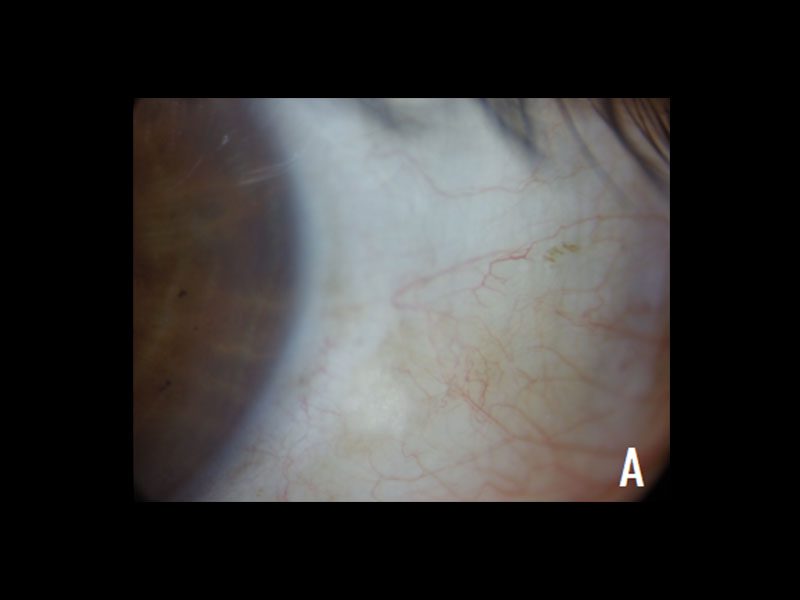

Paciente femenino de 68 años de edad, con antecedentes de hipertensión arterial, hemicolectomía derecha con resección de íleon terminal por cáncer de colon derecho hace 7 años. Como antecedentes oftalmológicos presentaba cirugía de catarata hace 5 años, colocación de plugs, 3 sesiones de luz pulsada intensa, 2 sesiones de iLux, tratamiento con ciclosporina y lágrimas artificiales sin resultados. Consulta por sensación de cuerpo extraño de años de evolución a predominio en el ojo izquierdo. Al interrogatorio dirigido la paciente refiere ceguera nocturna de meses de evolución. Al examen oftalmológico su agudeza visual en ambos ojos era 20/20, a la biomicroscopía presentaba superficie sin alteraciones, BUT normal, pseudofaquia. Ojo izquierdo lesión blanquecina, levemente sobreelevada, con aspecto de espuma de jabón intralesional en conjuntiva temporal inferior cercana al limbo, compatible con mancha de Bitot (Figura 1). El test de Schirmer resultó normal en ambos ojos y en cuanto al test con proparacaína el dolor cede antes de los 5 segundos por lo que se descarta neuropatía corneal. Se evidenció Vitamina A sérica menor a 0.3mg/dl en los estudios de laboratorio. Ante el cuadro oftalmológico con síntomas de ojo seco, sumada la ceguera nocturna, la presencia de mancha de Bitot y los niveles séricos bajos de vitamina A, junto al antecedente de cirugía de resección intestinal amplia por cáncer de colon se arriba al diagnóstico de Hipovitaminosis A por causa malabsortiva con manifestaciones oftalmológicas.

Figura 1 Mancha de Bitot verdadera Lesión levemente sobreelevada en conjuntiva bulbar temporal cercana al limbo. A Lesión blanquecina con aspecto de espuma de jabón en superficie. B Resalta con tinción de fluoresceína. C Visualizada con luz azul.